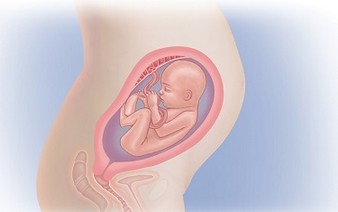

Расположение плода на 15-й неделе беременности: фотографии и иллюстрации

Раздел: Идеи и советы